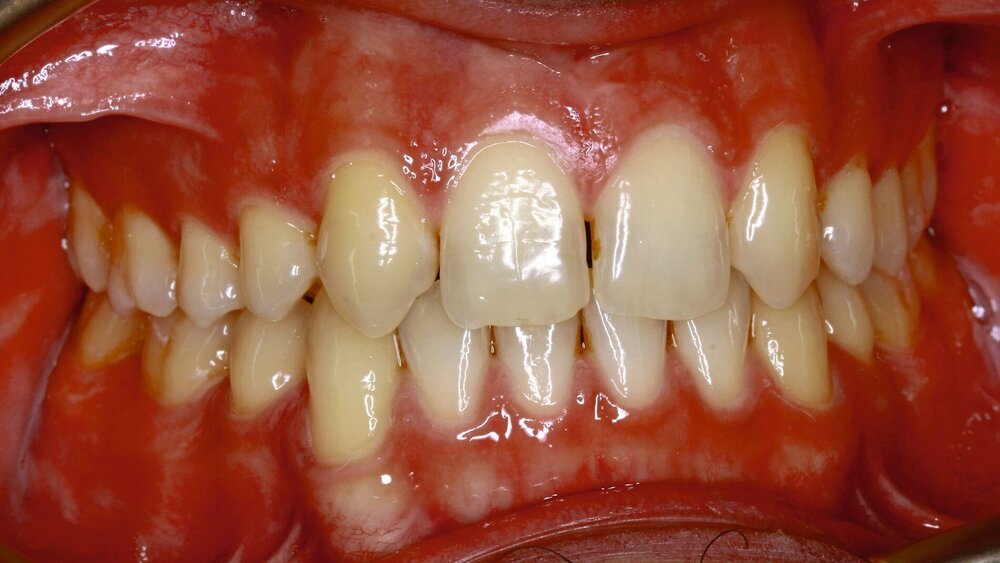

Im klinischen Befund zeigten sich eine Klasse-III-Verzahnung mit retralem Zwangsbiss sowie das Fehlen der Zähne 12, 22, 34 und 44 (Abbildung 1). Es wurde eine vollständig virtuelle Planung der Rotation-Advancement-Operation durchgeführt, bei der Ober- und Unterkiefer um 10 mm nach vorne verlagert wurden, um die pharyngealen Atemwege zu erweitern.